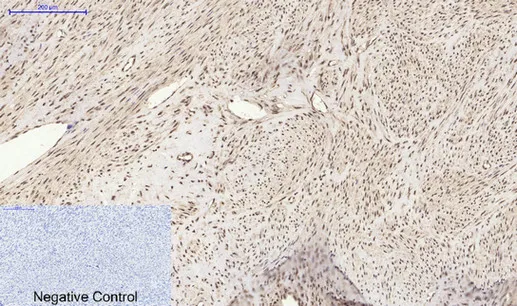

FOXP1 Rabbit Polyclonal Antibody

Cat: APRab11113

Size1:50μl Price1:$118

Size2:100μl Price2:$220

Size3:500μl Price3:$980

Size2:100μl Price2:$220

Size3:500μl Price3:$980